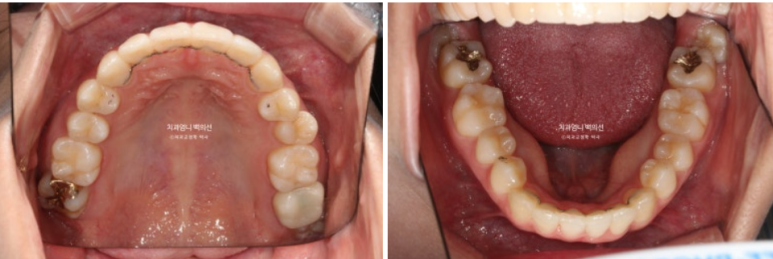

부분교정에서는 앞니 배열될 공간을 소량의 치간삭제로 얻습니다.

앞니부분교정용 장치 중 MTA 장치를 선택하셨고 치료에 들어갔습니다.

MTA 장치는 송곳니부터 송곳니까지 앞니에만 붙여서 배열을 진행했고 나머지 작은어금니와 큰어금니는 움직이지 않았습니다.

아무래도 파란 화살표 작은어금니 덧니가 옥의티입니다.

아쉽지만 환자분이 투자한 비용과 시간, 노력 대비 앞니 부분교정만으로도 좋은 효과 봤으니 눈을 질끈 감습니다.